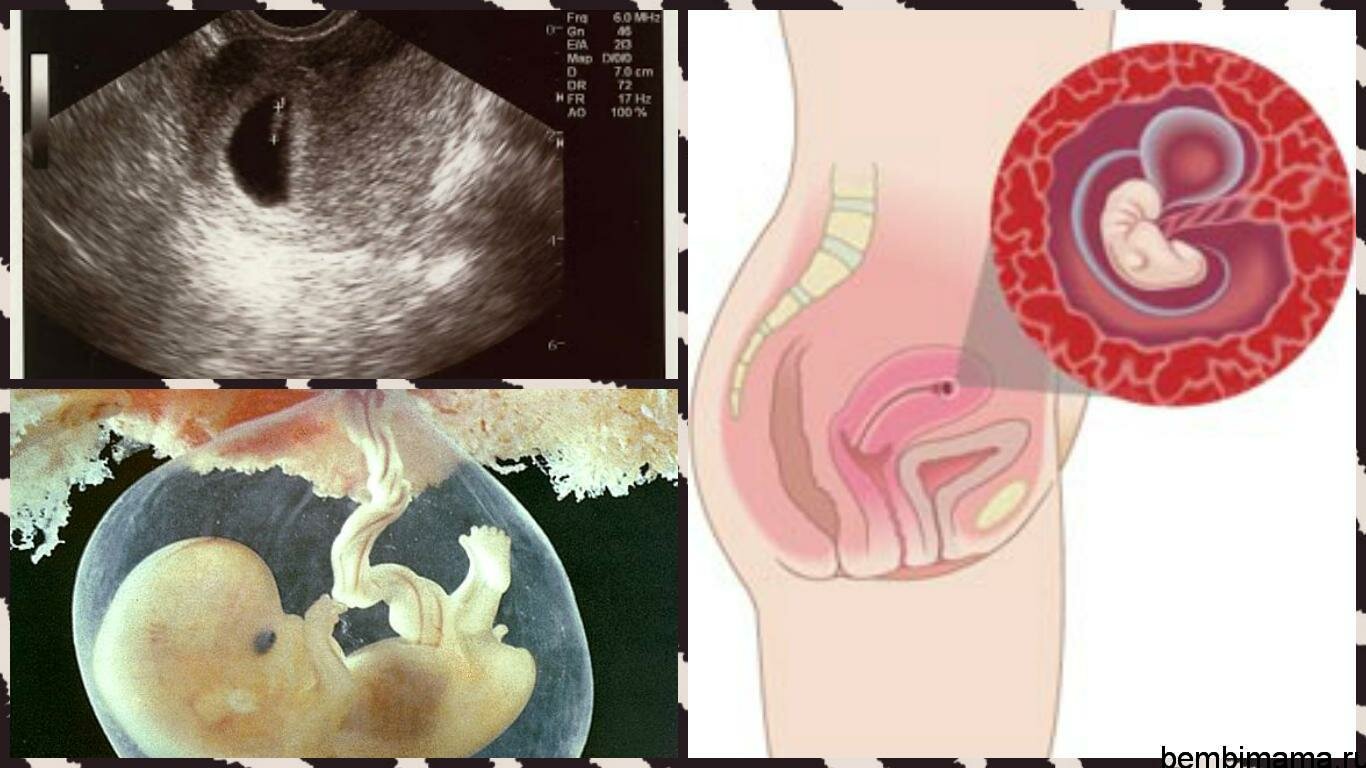

Развитие эмбриона: Что происходит на 3 неделе беременности

Раздел: Фотопанорама